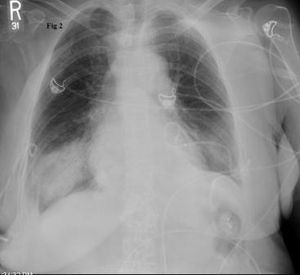

Worsening respiratory symptoms and fatigue of 6 months’ duration brought a 44-year-old woman in for evaluation. Diagnosed with asthma 2 years earlier, she was compliant with, but unresponsive to treatment. Your impressions?